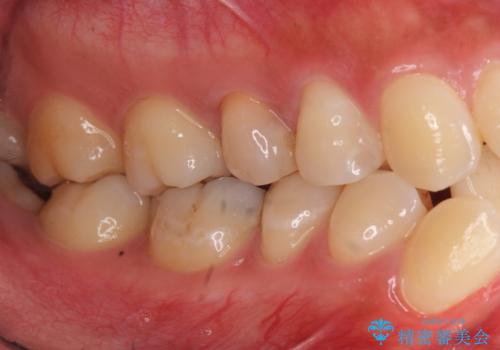

左上の奥歯はすれ違っていたためそのかみ合わせも整えています。

歯を抜いて治療を行ったため、Eラインが整った形で治療ができました。口が断然閉じやすくなっています。